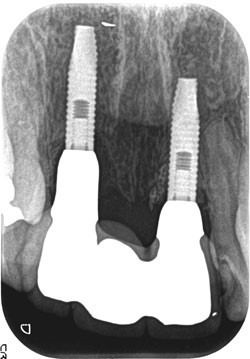

症例230代 男性 左上5 副鼻腔膜を挙上しインプラントを埋入

治療前

治療後(1年経過)

主訴 根尖病巣を長期放置していた為、抜歯。年齢を考慮し、インプラントを選択。

骨高不足の為、ソケットリフト(骨造成)を採用。

採血により得たCGFメンブレンとAFGブロック(人工骨β-TCPとAFGを混ぜたブロック)を填入し、副鼻腔の洞底膜を6㎜挙上後、インプラント体を埋入。

約4ヶ月間の免荷期間を経て、ジルコニアを装着。

リスクとしては、外科的侵襲がある。デメリットは、保険外診療の為、経済的負担がある。

費用 69万(税込)(オペ・ソケットリフト・人工骨・採血による濃縮血小板生成・仮歯・最終補綴物まで含む)